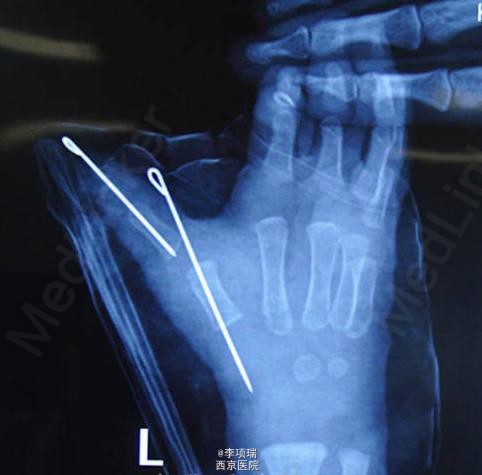

先天畸形:指骨及掌骨同时截骨矫形的多指切除术

患儿,男,1岁两月,左拇多指伴主干指三节拇、IP尺偏、掌骨分叉、MP尺偏。切除多指同时指骨及掌骨截骨矫形克氏针固定。